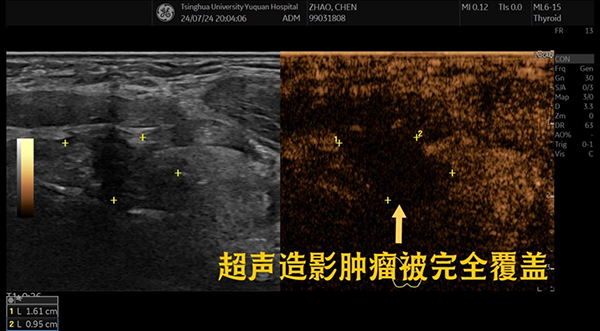

卜云芸主任为该患者制定了详细的治疗方案:在局麻下,先抽吸出结节中的囊液,并用生理盐水反复冲洗,再用95%的酒精进行硬化治疗,随后注射隔离液充分保护周围重要组织,超声引导下精准地将消融针置于结节处,逐层进行移动式消融,使整个结节的囊壁高温凝固坏死。从准备工作到消融结束不到半个小时,术中患者几乎没有疼痛感。术后即刻进行超声造影,该囊实性结节已被完全覆盖消融。患者当即表示颈部的压迫感已消失,呼吸顺畅了很多。

消融后